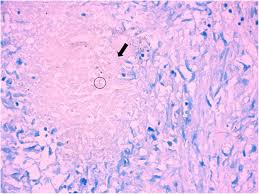

Tuberculosis Cancer Therapy Advisor from www.cancertherapyadvisor.com You can get tb by breathing in air droplets from a cough or sneeze of an infected person. A soft friction rub in early dry pleurisy may be mistaken for crepitation or fine bubbling rales but is not altered by coughing d. Pulmonary tb is caused by the bacterium mycobacterium tuberculosis (m tuberculosis). Primary tuberculosis clinical forms the primary site of infection in the lungs is called the ghon focus. Tb and lung cancer have been confused and misdiagnosed for centuries 2. 90% of cases being attributable to smoking. Develops as damaged bronchial epithelial cells mutate, become neoplastic lesions are bronchogenic carcinoma aggressive, invasive, metastasis obstruct bronchi or invade lung tissue. Tuberculosis is curable and preventable.

Selection of the most suitable tests for detection of m. Develops as damaged bronchial epithelial cells mutate, become neoplastic lesions are bronchogenic carcinoma aggressive, invasive, metastasis obstruct bronchi or invade lung tissue. In the past, it was well known that lung cancer is a specific epidemiological successor of ptb and that lung cancer often develops in scars caused by ptb. Pleural effusion may develop in lung cancer, breast cancer, lymphoma, lymphogranulematosis, benign and malignant pleural mesothelioma, bacterial 3.2. It is most commonly caused by aspiration of oral secretions by patients who have impaired consciousness. Tb and lung cancer have been confused and misdiagnosed for centuries 2. There is especially in countries with low tb incidence diagnostic challenges with risk of diagnosis getting missed. The occurrence of pulmonary tuberculosis (ptb) and lung cancer as comorbidities has been extensively discussed in many studies. Why has this disease, once thought to be confined to the. This means the bacteria are easily spread from an infected person to someone else. This is one reason that it is among the most deadly of cancer groups. Symptoms of tuberculosis and lung cancer are overlapping and it is difficult to differentiate without the histopathological report. Methods retrospective review of nsclc.

Difference between lung cancer and tuberculosis. This growth can spread beyond the lung by the process of metastasis into nearby tissue or other parts of the body. Selection of the most suitable tests for detection of m. However, this can also occur with tuberculosis or a pulmonary embolism. Concomitant active tuberculosis in nsclc (tblc) resembles locoregional immunotherapy of tumor cell vaccine; Primary tuberculosis clinical forms the primary site of infection in the lungs is called the ghon focus. Living with advanced breast cancer. Symptoms of tuberculosis and lung cancer are overlapping and it is difficult to differentiate without the histopathological report. When people with lung tb cough, sneeze or spit, they propel the tb germs into the air. Lung cancer and pulmonary tuberculosis (tb) comorbidity is a clinical problem that presents a challenge for the diagnosis and treatment of both diseases.objective: Tuberculosis (tb) is a potentially serious infectious disease that mainly affects the lungs. Primary tuberculosis usually begins in childhood and affects the lungs and bronchial lymphatic glands of the lung roots. You can't get it from shaking hands with someone who has it or by sharing their food or drink.